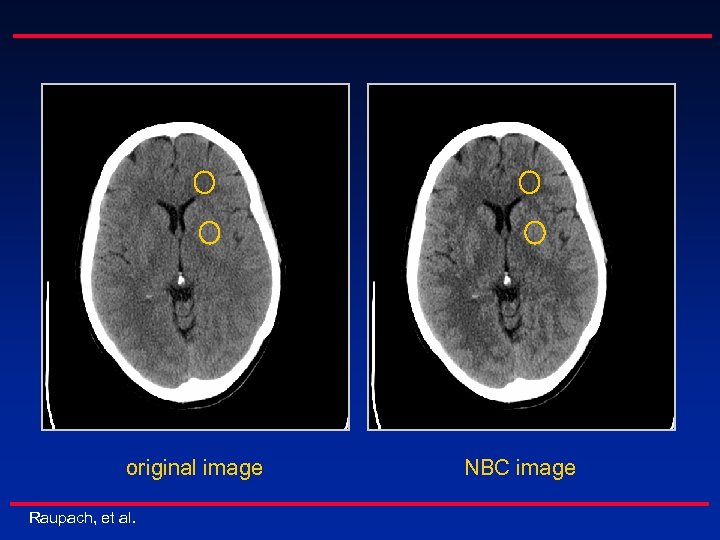

n Facts Diagnostic value of CT images is limited by the available contrast-to-noise ratio (CNR) n CNR is small particularly for soft tissue (with low contrast) n CNR improvement by higher dose is undesirable n n Analysis Image noise is dominated by high spatial frequencies n Soft tissue representation (low contrast detectability) mainly depends on medium/low frequencies Image enhancement by frequency band-selective processing n Raupach, et al.

original image Raupach, et al. NBC image

n MBE improves CNR of specific image features n n Head: gray/white matter differentiation (CNR gain up to ~40%) CNR improvement can be translated into radiation dose reduction n n 30% less dose demonstrated in example realistic in general: 20% (further clinical studies needed) Raupach, et al.